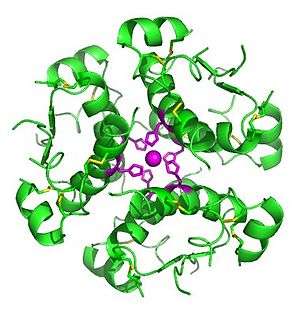

| Insulin (which this condition creates in excess) | |